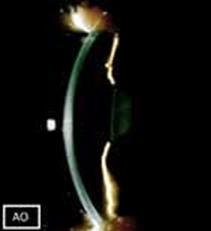

- Η οπτική τομογραφία συνοχής πρόσθιου ημιμορίου (AS-OCT) έδειξε αύξηση του εύρους της γωνίας (Εικόνα 4)

- Δεν υπήρχαν μετεγχειρητικές επιπλοκές κατά την τελευταία επίσκεψη παρακολούθησης (Εικόνα 5)